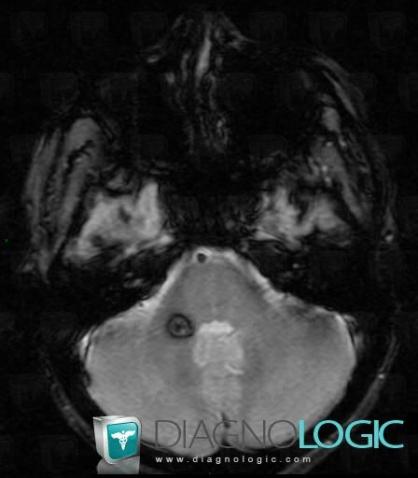

Cavernous angioma, Brainstem, MRI

Here is the specific information in the key image above:

- Diagnosis Cavernous angioma, Location(s) Brainstem, with gamuts